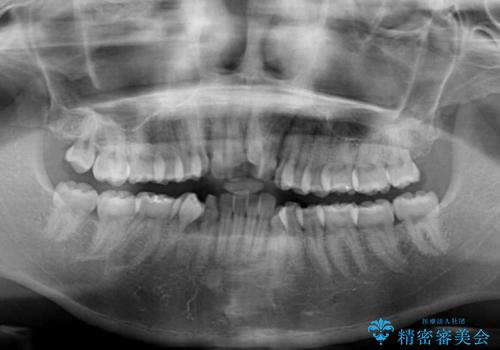

- 前歯のデコボコと口元の突出感を気にして来院された患者様です。

上下左右第一小臼歯4本を抜歯し、ワイヤー装置にて口元を引っ込めるよう矯正治療を行うこととしました。

叢生が強かったため、口元の突出感の改善には限界がありましたが、横側からも口元が引っ込んだ感じが分かるほど改善されました。